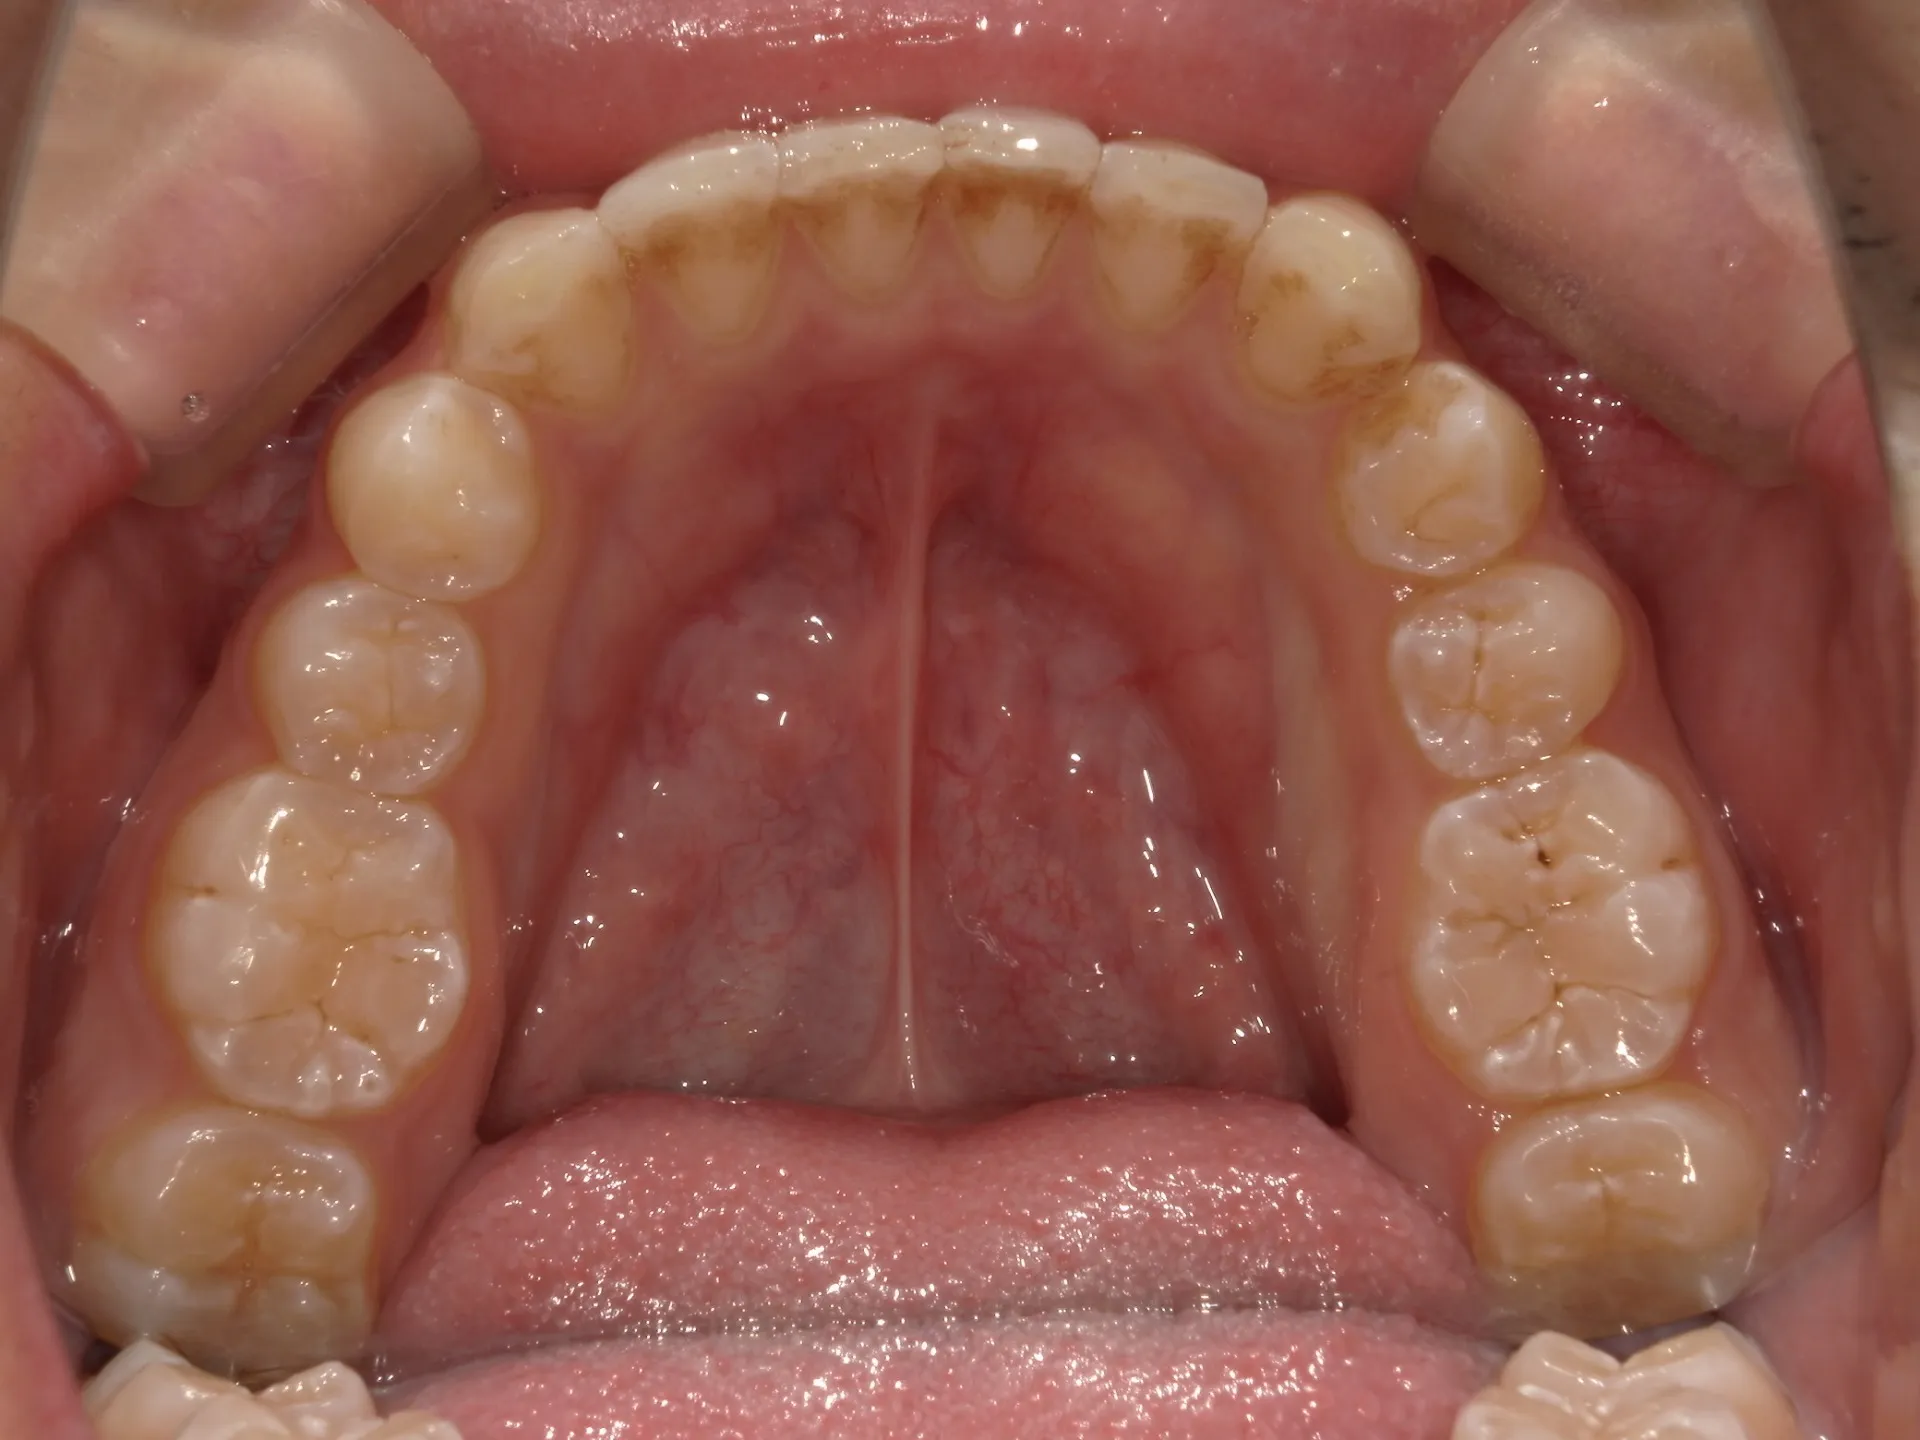

今回は他院さんでインビザライン矯正治療を受けていた患者様を引き継いで当院でインビザライン治療を継続した症例をご紹介致します。

今回はマウスピース矯正を主軸にした矯正ですが、一部ワイヤー矯正も併用して改善しております。